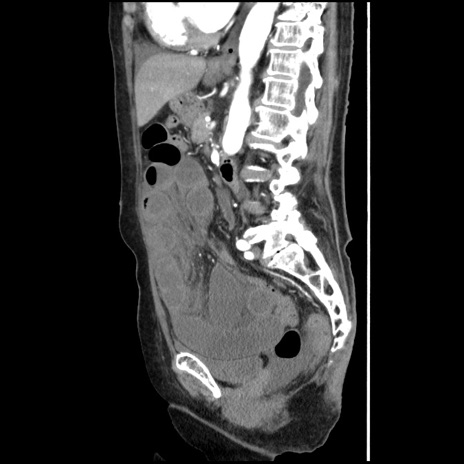

症例1(矢状断像)

【症例】80歳代女性

【主訴】腹痛

【現病歴】8時間前から腹痛あり来院。

【既往歴】糖尿病、脂質異常症、子宮体癌にて子宮全摘術

【身体所見】意識清明・会話良好だが腹痛で苦悶様、全腹部にわたって反跳痛と圧痛あり

【データ】WBC 13600、CRP 0.14、LDH 224、CK 90